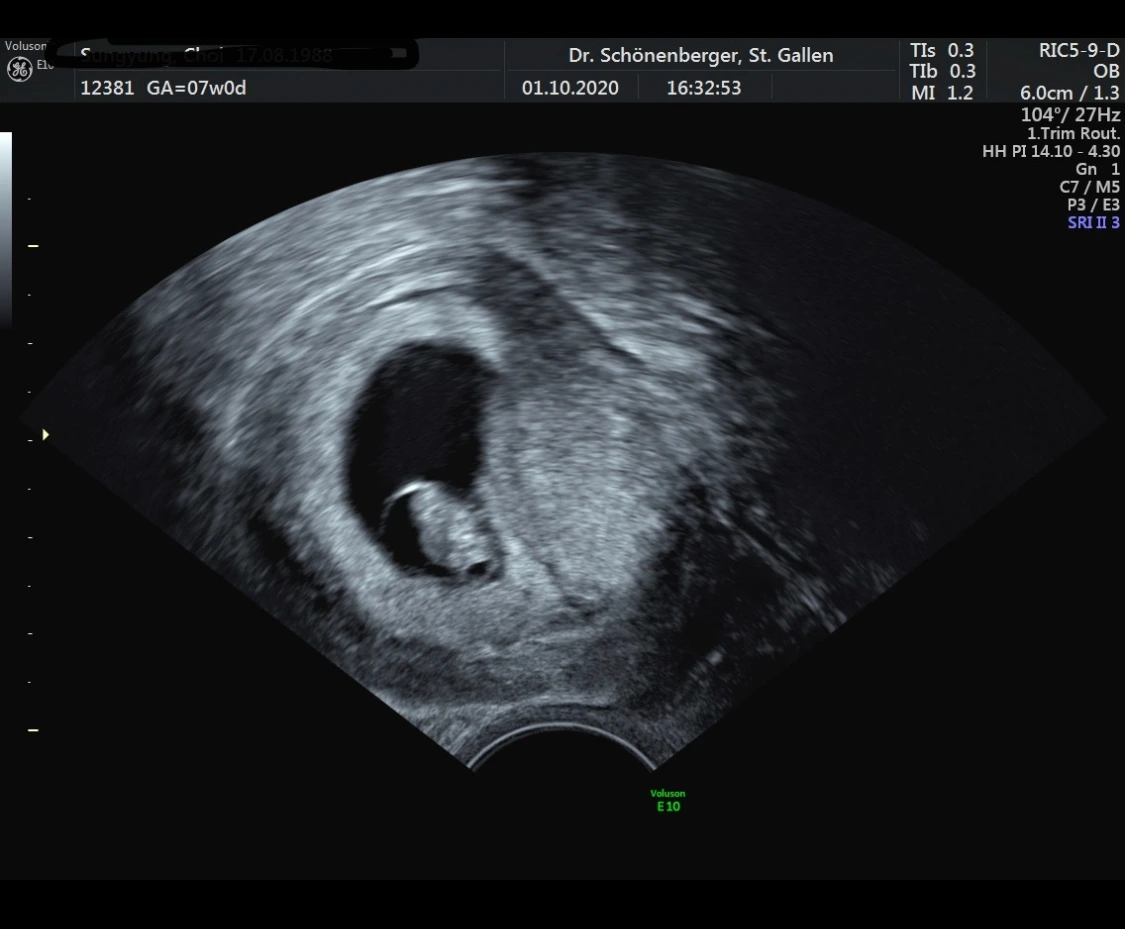

그러고 나서 초음파 검사를 했고 아기의 심장이 뛰는 것과 아기집을 확인할 수 있었는데 한국에서 처럼 소리를 들을 수는 없었다.